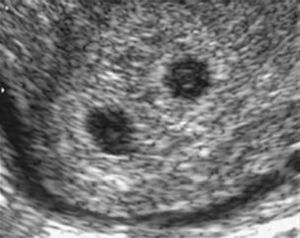

First trimester The ideal time to determine chorionicity is the first trimester. As early as 4–5 weeks postmenstrual weeks, by using transvaginal sonography, it is possible to recognize the chorionic sacs inside the uterine cavity within the tick deciduas. They appear as sonolucent round structures with a brightly echogenic rim. By simply counting the chorionic sacs it is possible to establish whether the pregnancy will be monochorionic, dichorionic, trichorionic and so on (Fig. 1).

The visualization of a single chorionic sac at 4–5 weeks, however, does not exclude the possibility of a monochorionic twin pregnancy. By the sixth postmenstrual week the yolk sac and the embryo can be visualized inside the chorionic sac and the definitive diagnosis of a single pregnancy or monochorionic twin pregnancy can be done. If a single chorionic sac is visualized containing two yolk sacs and two embryonic poles, then a monochorionic twin pregnancy can be diagnosed (Fig. 2).